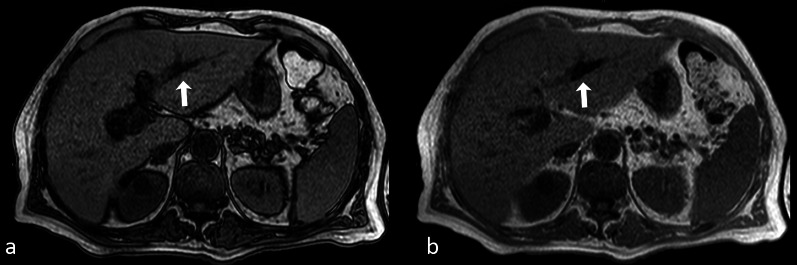

Axial opposed-phase (a) and in-phase (b) GE images showing a linear susceptibility-related artifact in the left hepatic duct, consistent with pneumobilia. The hypointensity is more conspicuous on the in-phase image

The presence of molecular oxygen in the air contributes to the susceptibility effects in every pathologic process containing gas, like abscesses or pneumobilia (Fig. 6).

Fig. 6.